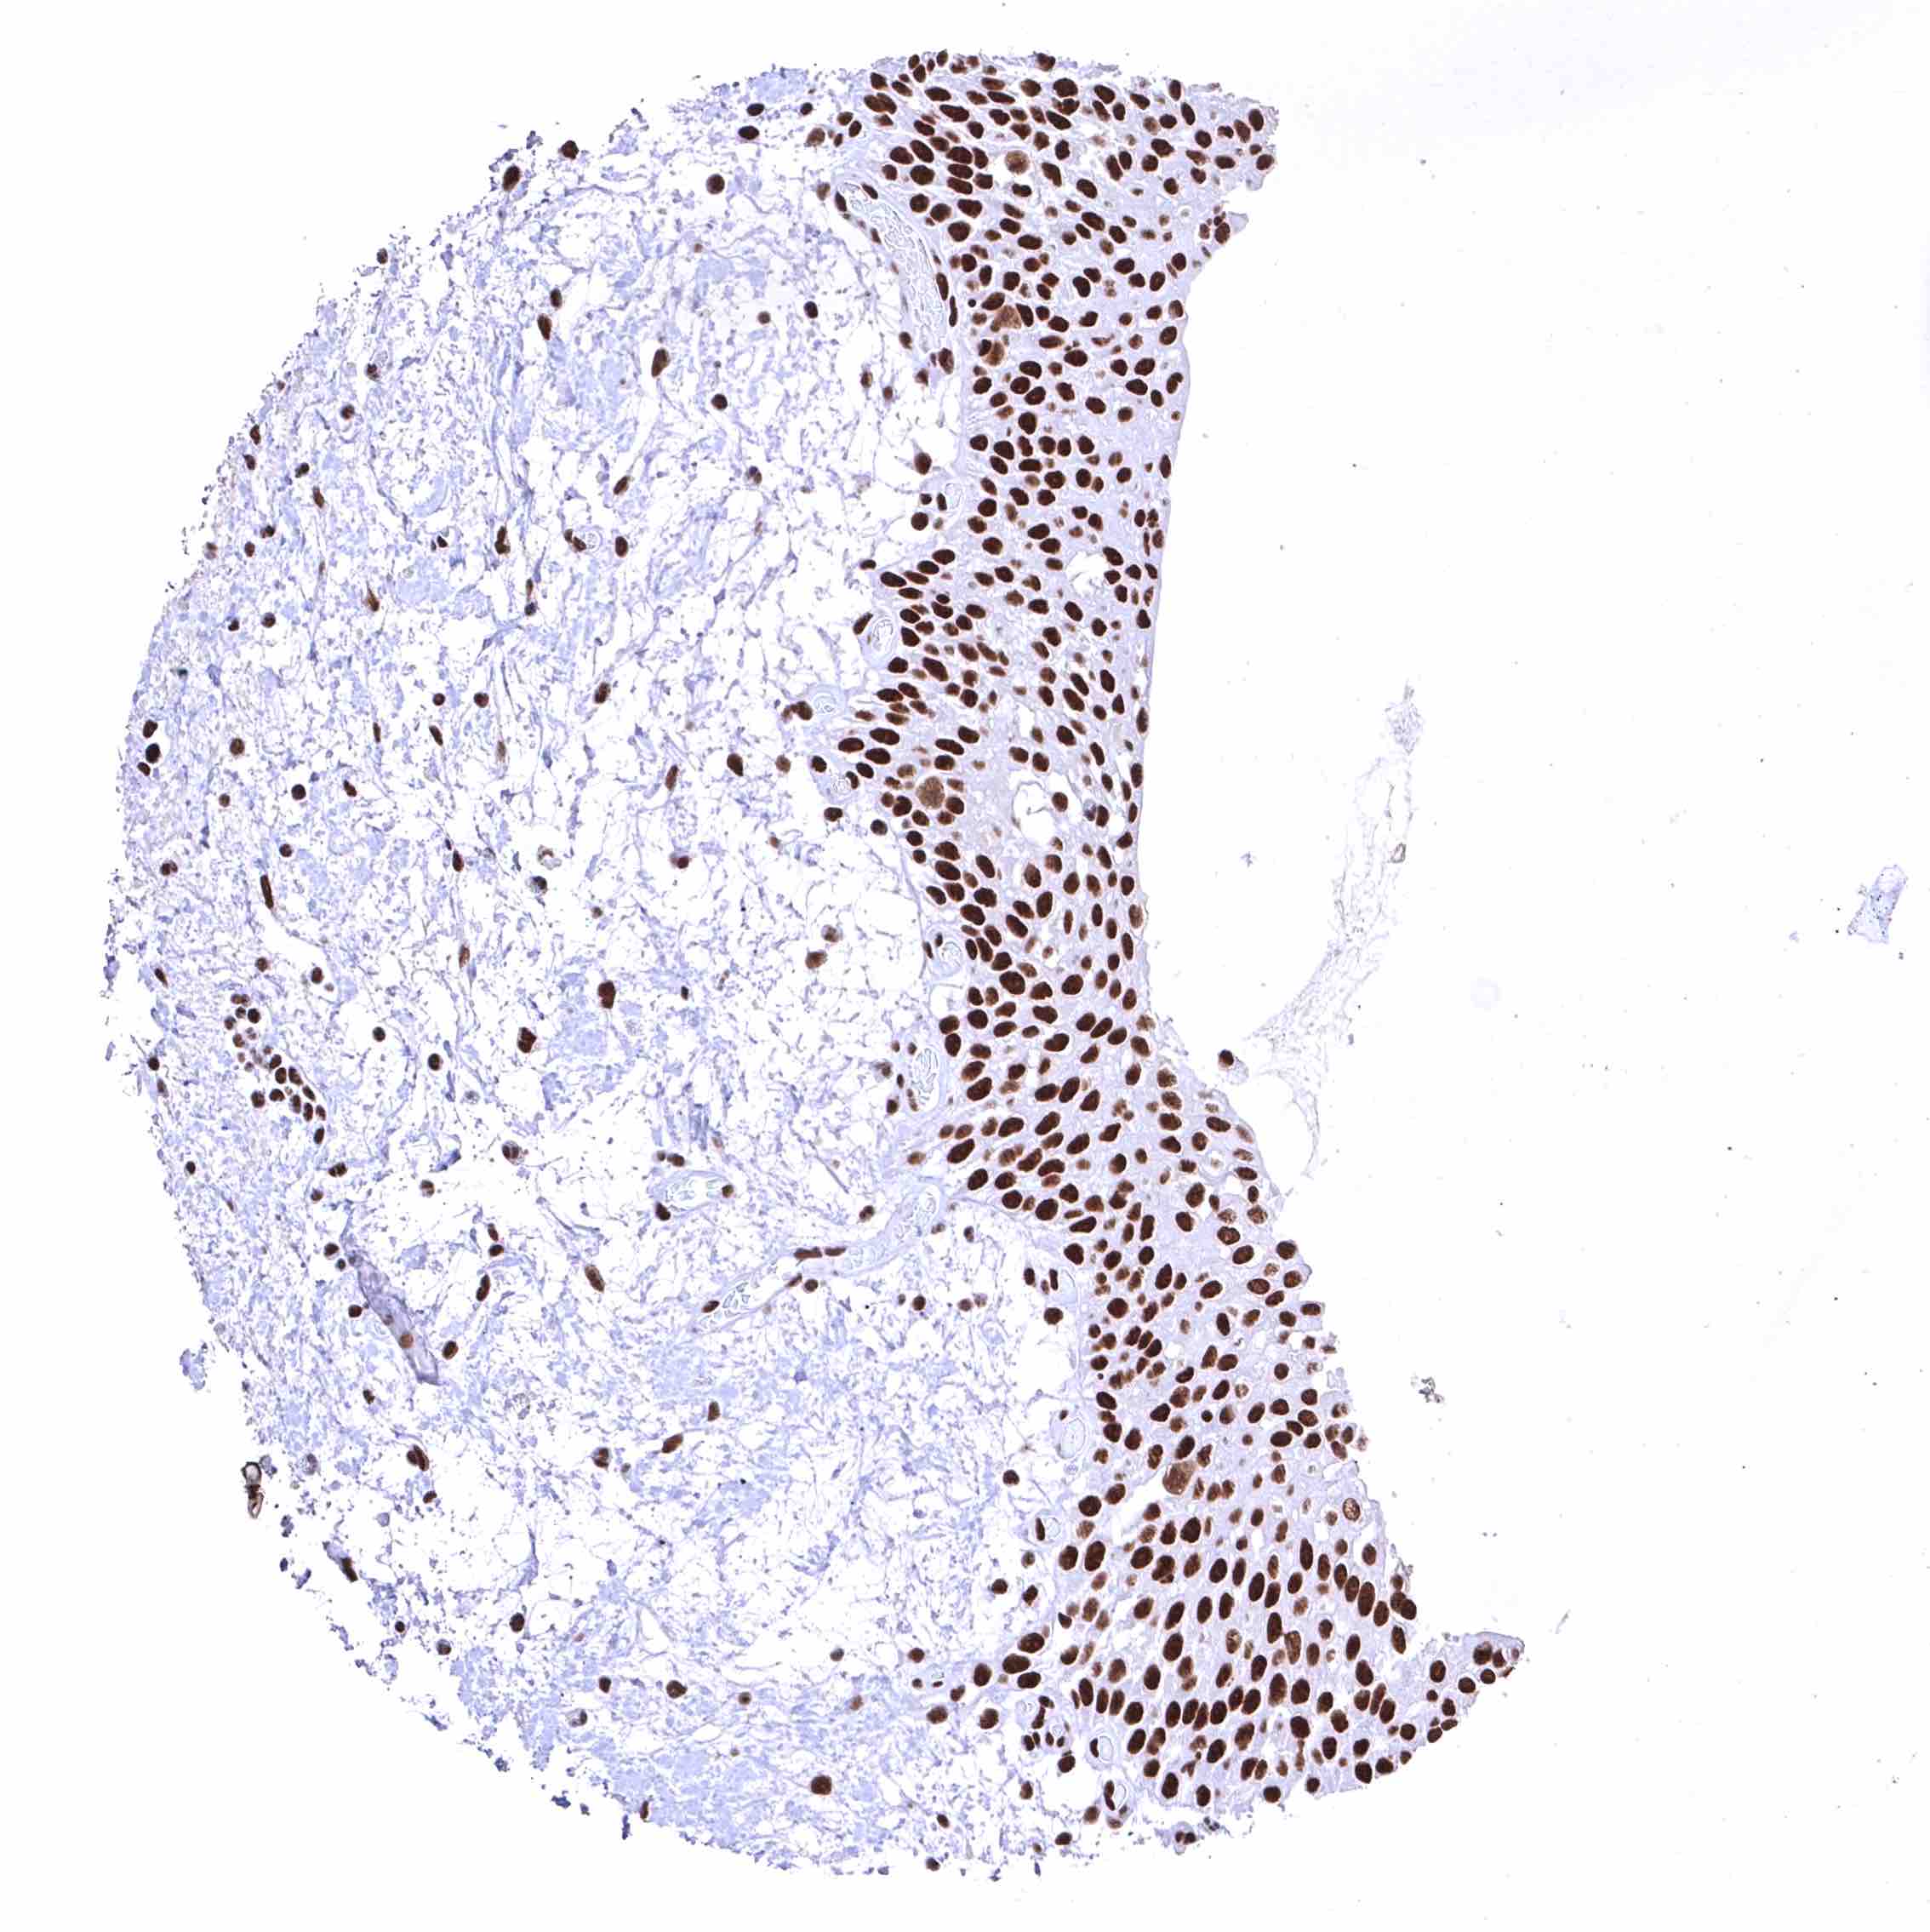

BRD4 antibody [HMV4275] HistoMAX™

Esophagus, squamous epithelium – Distinct nuclear BRD4 staining of squamous epithelial cells with a slight decrease of the staining intensity towards the most superficial cell layers.